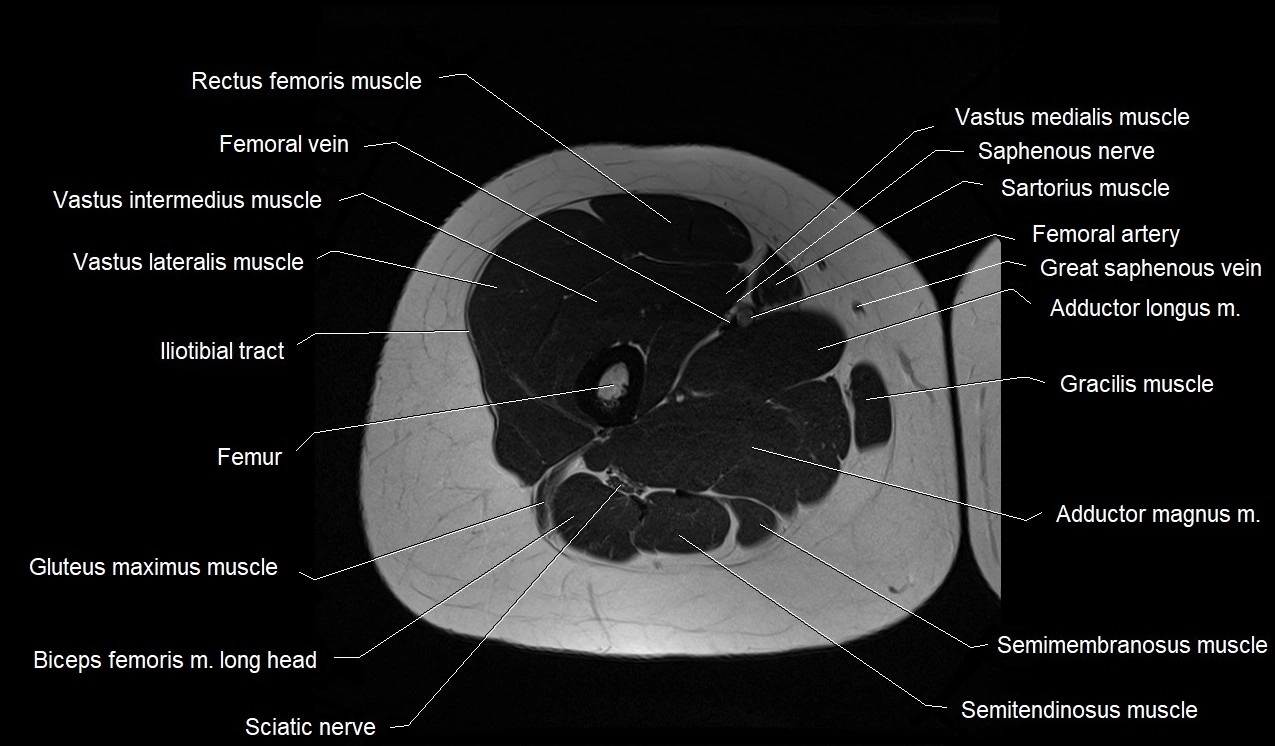

- Biceps femoris muscle (Long head)

- Biceps femoris muscle (Short head)

- Femoral artery

- Femoral vein

- Femur

- Gluteus maximus muscle

- Gracilis muscle

- Iliotibial tract

- Rectus femoris muscle

- Saphenous nerve

- Sartorius muscle

- Semimembranosus muscle

- Semitendinosus muscle

- Vastus intermedius muscle

- Vastus lateralis muscle

- Vastus medialis muscle